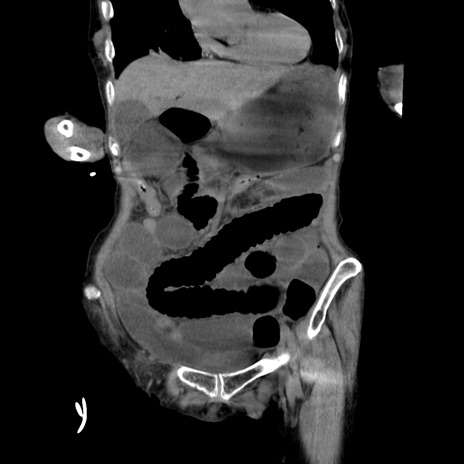

症例27(冠状断像)

【症例】80歳代女性

【主訴】嘔吐、腹痛

【現病歴】数時間前より嘔吐あり。心窩部痛出現し、徐々に右下腹痛あり。その後も数回嘔吐あり救急搬送となる。

【既往歴】左大腿骨頚部骨折手術

【身体所見】腹部は膨隆しているが軟らかく圧痛なし。腸雑音はやや亢進。

【データ】WBC 12000、CRP 19.05